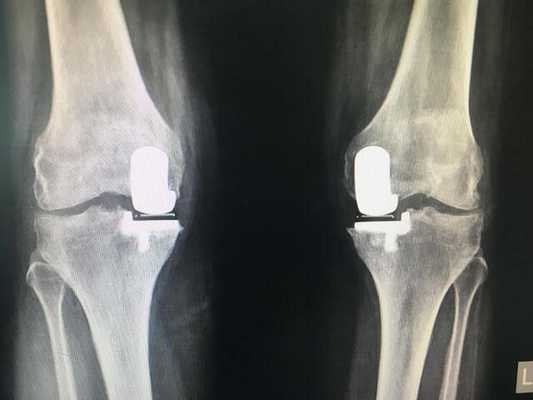

Одномыщелковая замена сустава на рентгене.

Сравнение двух типов операций.